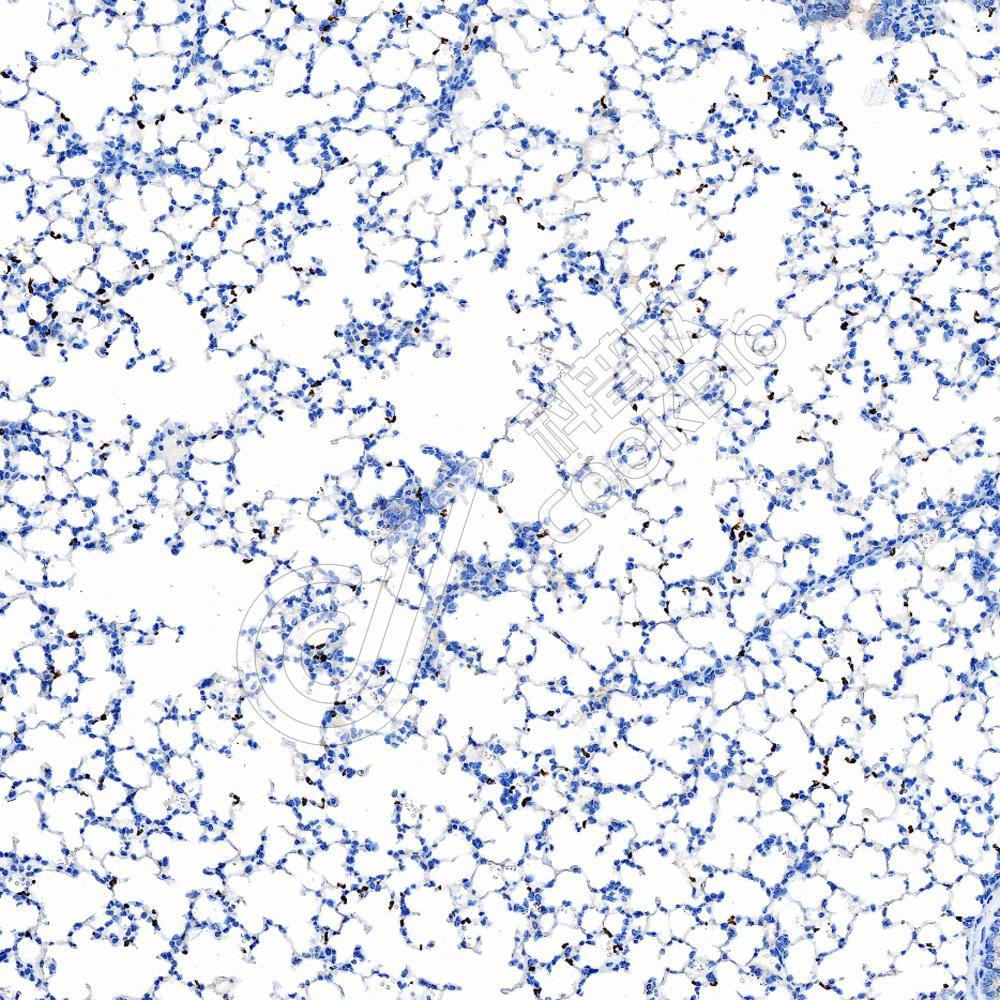

IHC检测PADI4/PAD4蛋白(货号 K5450306).

样品: 小鼠肺, 4%多聚甲醛 (货号KSG1101) 固定12-24小时.

抗原修复: Tris-EDTA抗原修复液(pH 9.0) (货号KSG1203), 水浴100℃, 25分钟.

—抗: 1: 600稀释, 4℃ 孵育过夜.

二抗: S-vision免疫组化多聚二抗(山羊抗兔),即用型 (货号KB3906), 室温孵育20分钟.